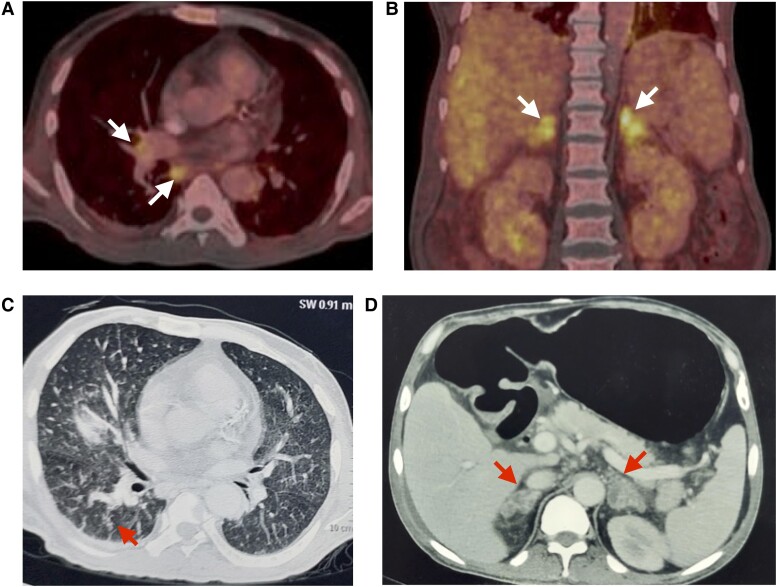

高钙血症是一种相对常见的临床问题,对其病因进行评估往往具有挑战性。然而,彻底的病因检查可以指导有效的治疗,而且往往可以挽救生命。我们描述了一名 61 岁男性的病例,他发热、厌食和体重减轻持续了 3 个月,感觉改变持续了约 1 周。对他的评估显示他患有严重的高钙血症,纠正高钙血症后症状有所改善。病因检查发现,他患有甲状旁腺激素依赖性高钙血症,同时1,25-二羟维生素D水平升高,这提示他患有肉芽肿性疾病。放射学评估提示该病为多系统疾病,伴有双侧肾上腺肿大、全身淋巴结肿大和肝脾肿大。肾上腺和骨髓活检明确诊断为进行性播散性组织胞浆菌病,需要使用两性霉素 B 脂质体进行为期 4 周的治疗,随后口服伊曲康唑。治疗有效后,血钙恢复正常,症状消失。组织胞浆菌病是导致高钙血症的罕见病因,全世界仅报道过约 22 例此类病例。

Hypercalcemia is a relatively common clinical problem, and evaluation for its etiology may often prove to be challenging. However, a thorough etiological workup can guide effective therapy and can often prove to be lifesaving. We describe a 61-year-old man who presented with fever, anorexia, and weight loss for 3 months, and altered sensorium for around 1 week. His evaluation revealed severe hypercalcemia, correction of which led to improvement in his symptoms. Workup for the cause revealed that he had parathyroid hormone-independent hypercalcemia with elevated levels of 1,25-dihydroxyvitamin D, suggesting a granulomatous disease. Radiological evaluation was suggestive of a multisystem disorder with bilateral adrenal enlargement, generalized lymphadenopathy, and hepatosplenomegaly. Biopsy from the adrenal gland and bone marrow clinched the diagnosis of progressive disseminated histoplasmosis, which required treatment with liposomal amphotericin B for a total duration of 4 weeks, followed by oral itraconazole. The effective treatment was associated with normalization of serum calcium and disappearance of symptoms. Histoplasmosis represents a rare cause of hypercalcemia, with only around 22 such cases having been reported worldwide.